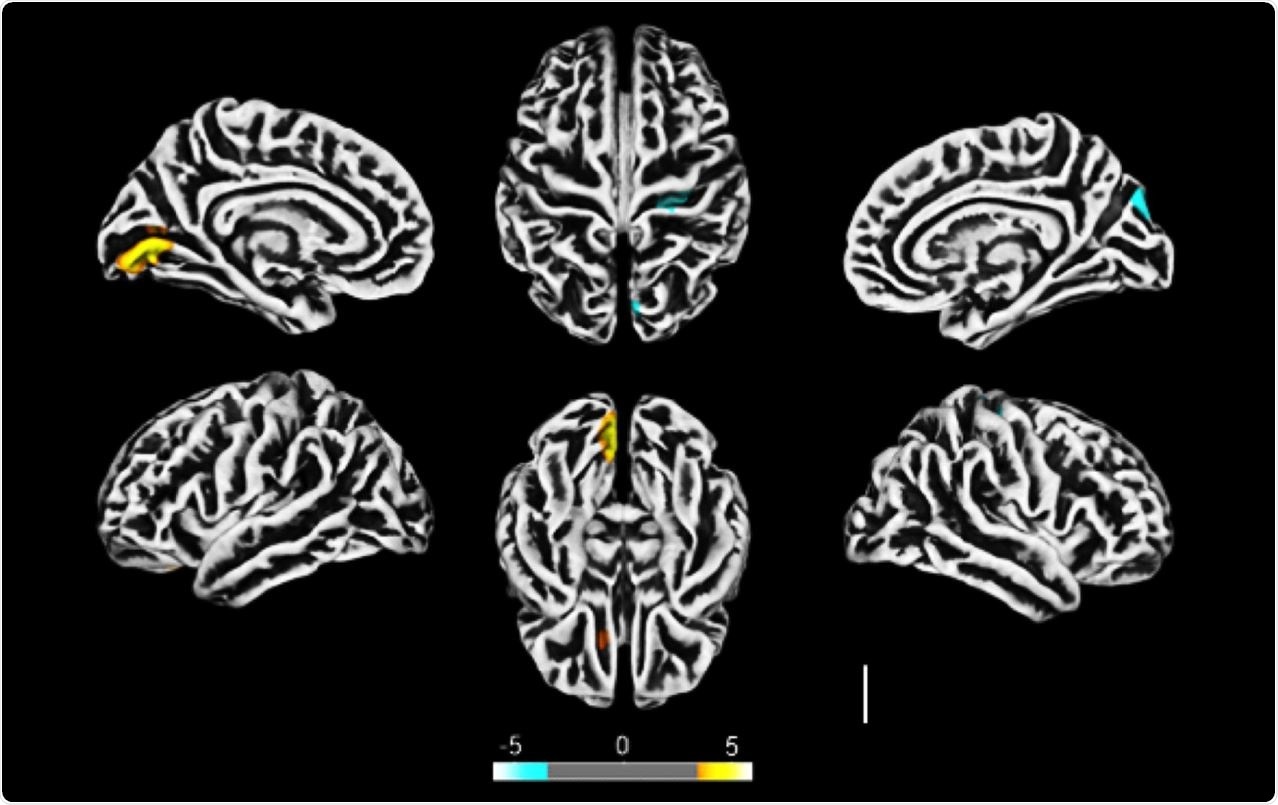

Altered cerebral cortical thickness is associated with neuropsychiatric symptoms in COVID-19 patients. a) Surface-based morphometry using high-resolution 3T MRI. Yellow represents areas of decreased cortical thickness: left lingual gyrus, calcarine sulcus (and cuneus), and olfactory sulcus (and rectus gyrus) . Blue represents areas of increased cortical thickness: central sulcus (precentral and postcentral gyrus) and superior occipital gyrus. Representative image of the analysis of 81 subjects tested positive for SARS-CoV-2 who had mild respiratory symptoms and did not require hospitalization or oxygen support compared to 145 healthy volunteers (without diagnosis of COVID-19) . The analysis was performed within a median interval of 54 days. b) Correlation between BAI performance and right orbital gyrus thickness. The data depicts Pearson’s correlation coefficient . c) Correlation between TRAIL B performance and right gyrus rectus thickness. Data depict Pearson’s correlation coefficient and region of interest in representative images.

All the recruited patients underwent MRI scanning of the brain. The team saw reduced cortical thickness in some areas of the brain and increased thickness in other parts.

Upon correlating the cortical thickness changes to the neuropsychological evaluation, the team found that the thinner cortex affected verbal memory, suggesting COVID-19 can affect brain structure and result in changed brain functions.

The changes were related to anxiety and cognition, indicating the virus affected the cortical region of the brain. The authors speculate that because one of how the virus affects nerves is via the olfactory nerves, it is possible that the effect of the virus on the cortical regions could be because it is closely associated with the olfactory nerves.